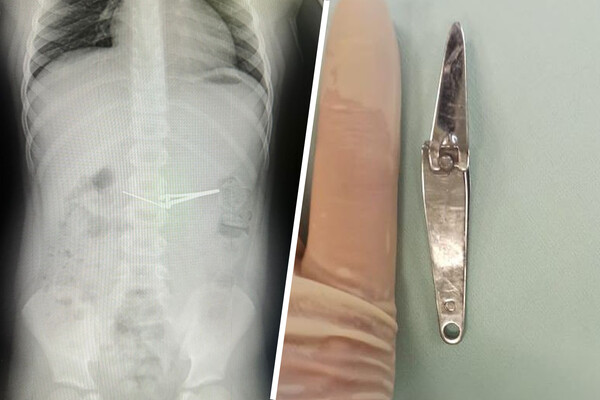

Щипцы для стрижки ногтей извлекли из желудка ребенка в Уфе

В Башкирии шестилетний ребенок проглотил щипцы для стрижки ногтей

Медики городской детской больницы №17 Уфы вытащили из желудка ребенка щипцы для стрижки ногтей. Об этом сообщает минздрав республики.

Инородное тело извлекали с помощью специальной эндокорзины, щипцы смогли подхватить и извлечь из желудка шестилетнего мальчика, не повредив при этом слизистую оболочку. Вмешательство проводилось под общим обезболиванием.